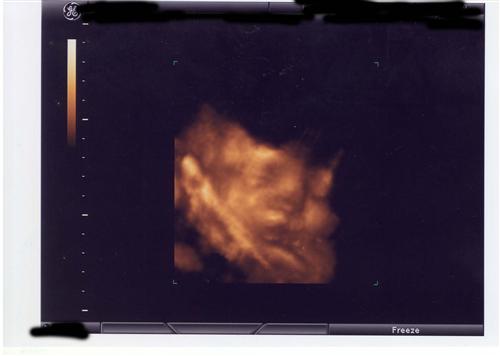

I had a 32 week ultrasound and unfortunately baby E was not cooperating and decided to put her/his arm over the face the whole time, no matter what we did. So the pictures are not the best, but tell me what you think! My DH is convinced it is a girl. We shall see!

Just going by the last pic (which is adorable by the way!) I am going to say